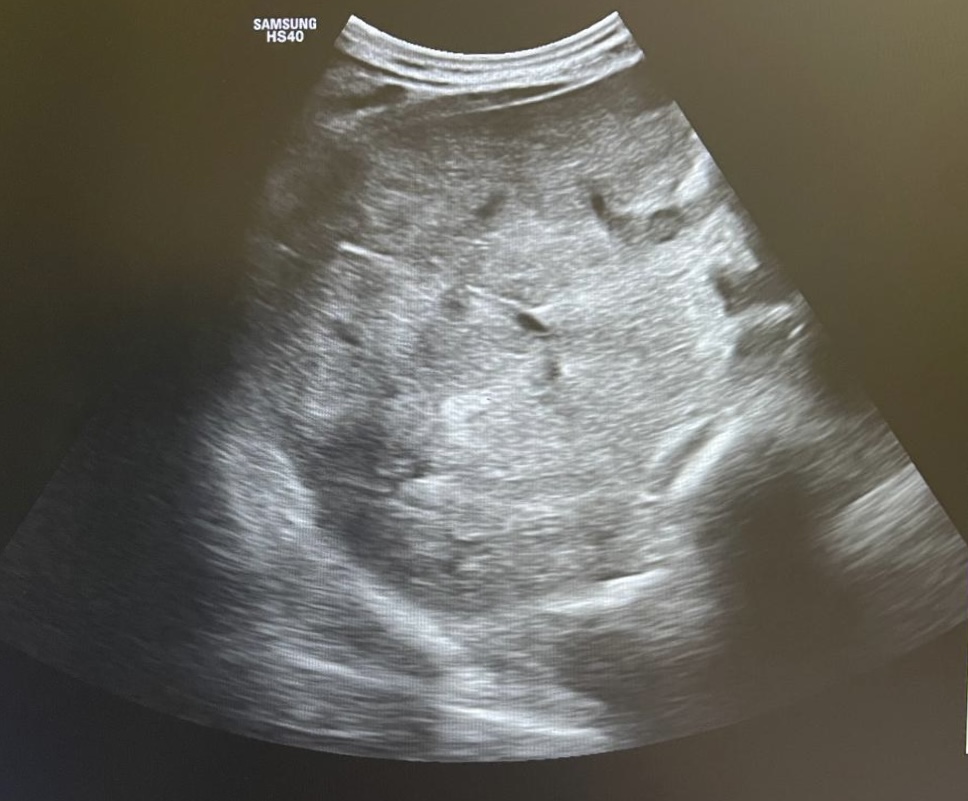

Hallazgos ecográficos

En la ecoscopia se observan múltiples nódulos hipoecoicos en el parénquima hepático sugestivos de afectación metastásica. Se solicita ecografía reglada preferente, confirmándose el hallazgo de nódulos hipoecogénicos de predominio en el lóbulo izquierdo hepático.